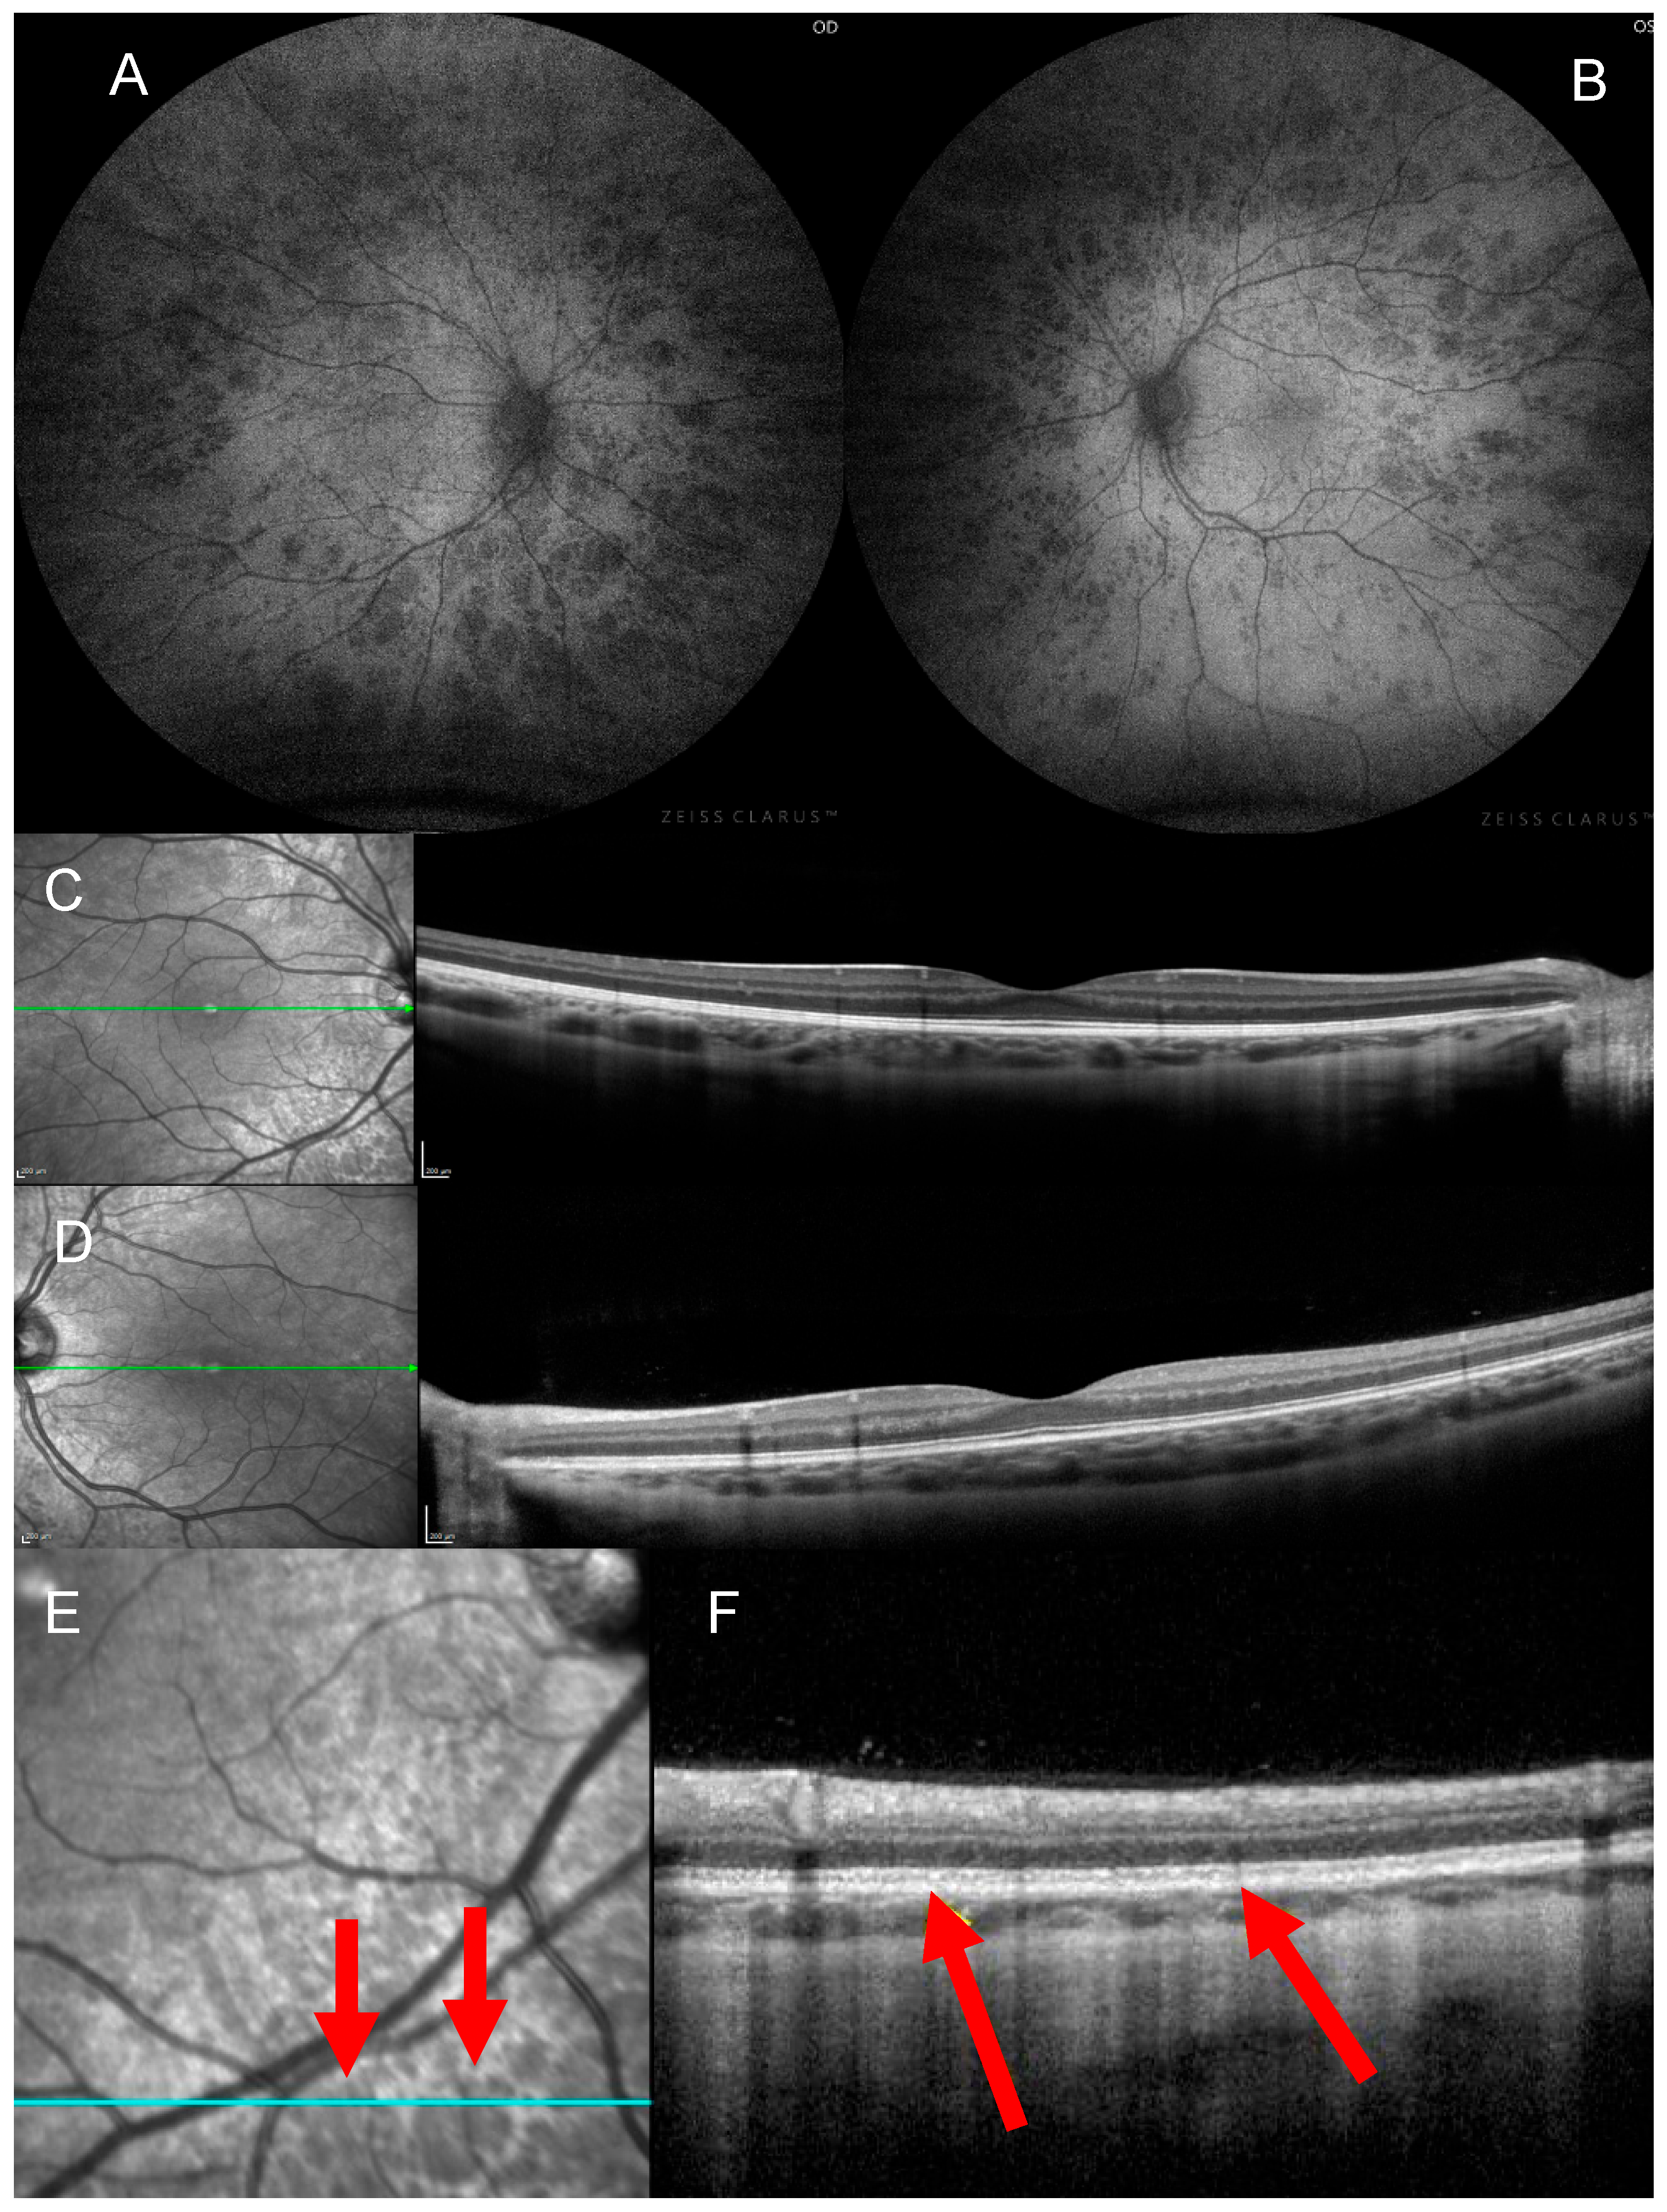

4. Clinical Findings

5. Investigations